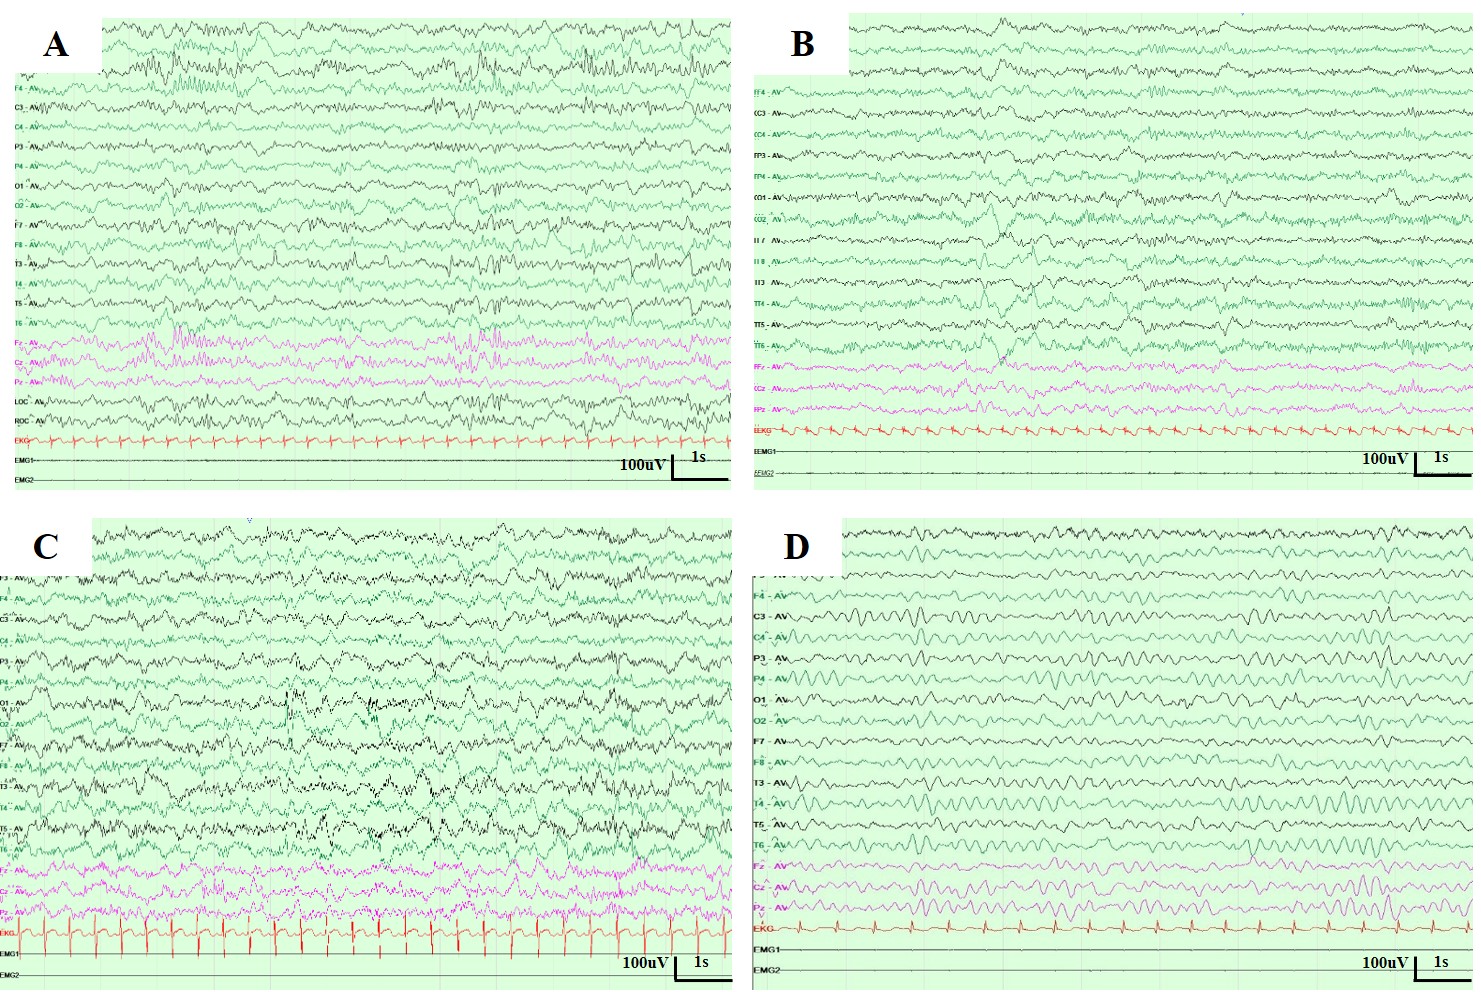

We present two unrelated Chinese patients with CAD deficiency manifesting with a triad of infantile-onset psychomotor developmental delay with regression, drug-refractory epilepsy, and anaemia with anisopoikilocytosis. Timely translation into uridine supplementation, within 2-months of disease onset, allowed us to stop conventional anti-epileptic drugs and led to dramatic improvement in the clinical symptoms, with prompt cessation of seizures, resolution of anaemia, developmental progress, and prevention of development of severe and non-reversible manifestations. The remarkable recovery and prevention of advanced disease with prompt treatment, highlights the need to act immediately upon genetic diagnosis of a treatable disease. This further reinforces CAD deficiency as a treatable neurometabolic disorder and emphasises the need for a biomarker or genetic new born screening for early identification.